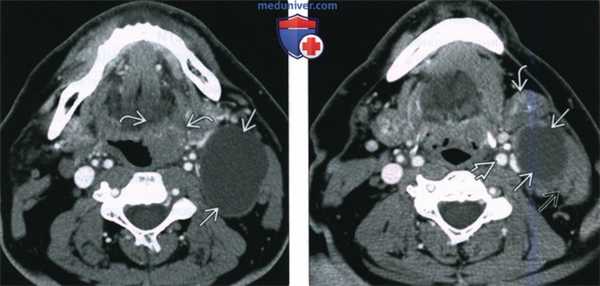

(Слева) На рисунке (в аксиальной плоскости) показан первичный ПКР небной миндалины. Опухоль располагается в боковой стенке ротоглотки и прорастает в переднюю небно-язычную дужку. Задняя небно-язычная дужка не инфильтрирована опухолью. Обратите внимание на увеличенный лимфоузел второго уровня на стороне опухоли.

(Справа) При аксиальной КТ с КУ у этого же пациента визуализируется объемное образование миндалины размером 1,8x1,0 см с гиподенсным участком в центре, верифицированное как высокодифференцированный ПКР. Наблюдается несколько увеличенных лимфоузлов на стороне поражения (стадия заболевания: IVA, стадия опухоли: T1N2b). Медиальное положение внутренней сонной артерии делает невозможной трансоральную роботизированную операцию. (Слева) На фотографии, выполненной при клиническом обследовании женщины с дисфагией и жалобами на боль в горле и ухе справа, видна изъязвленная и уплотненная правая небная миндалина. Обратите внимание на сглаженность правой передней небно-язычной дужки по сравнению с противоположной стороной.

(Справа) При МРТ Т1ВИ С+FS в аксиальной проекции у пациента с новобразованием шеи справа визуализируется верхний край конгломерата лимфатических узлов. Была выполнена тонкоигольная аспирация, подтвердился ПКР. Визуализируется также хорошо отграниченная первичная опухоль небной миндалины размером 2,2x1,8 см (T2N2b, стадия IVA).